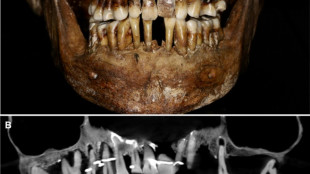

French aristocrat's golden dental secret revealed 400 years on

Scientists have discovered the long-buried secret of a 17th-century French aristocrat 400 years after her death: she was using gold wire to keep her teeth from falling out.